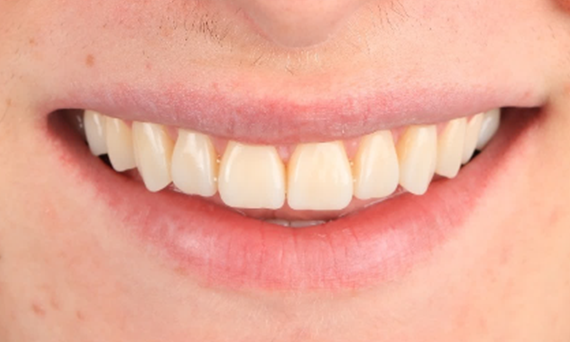

Amelogenesis Imperfecta

Full mouth rehabilitation with 28 all-ceramic restorations

A particular and protracted case of skeletal Class II malocclusion and generalized amelogenesis imperfecta in a teenager was referred for prosthetic rehabilitation. The aim of the treatment was to prepare the remaining tooth structure, remove undercuts, and make room for all-ceramic crowns covering the entire dentine and simulating the lost enamel.

Before: Initial situation prior to orthodontic treatment.

After: Final result, 1 week post-operative.

Alexander Declerck, (DDS, MSc)

Sint-Martens-Latem, Belgium